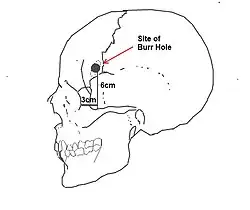

Егоров предложил свою модификацию лоботомии. Вместо закрытого доступа через фрезевое отверстие или крышу орбиты он использовал костно-пластическую трепанацию, дававшую широкий обзор операционного поля и позволявшую точнее ориентироваться в определении мишени хирургического вмешательства. Лоботомия осуществлялась щадяще, как правило только в одной лобной доле, её полюсных отделах и всегда спереди от переднего рога бокового желудочка и подкорковых узлов. При такой методике исключались повреждения пирамидных путей и подкорковых образований[31].

Новое направление в 1940-е годы в Ленинграде развивал нейрохирург профессор Исаак Бабчин. Он разработал щадящий хирургический доступ для выполнения лоботомии. Для подхода к лобным долям накладывались фрезевые отверстия парасагиттально. Далее лейкотомом оригинальной конструкции осуществлялось повреждение фронто-таламических путей. Свою операцию Бабчин назвал «фронтальной лейкотомией». Одновременно развернулись исследования по изучению анатомии и топографии корково-подкорковых путей. М. С. Короткевич в своей кандидатской диссертации уточнила связи коры больших полушарий с подкорковыми ядрами. А. А. Вагина в своей докторской диссертации обосновала лоботомию, успев до запрета выполнить важные фрагменты: «Анатомический анализ экспериментальной лейкотомии» и «Связи лобной доли с таламусом»[31].